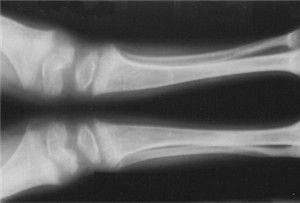

放射医学(医学高级):X线考试题库(强化练习) - 考试题库 - 91考试网